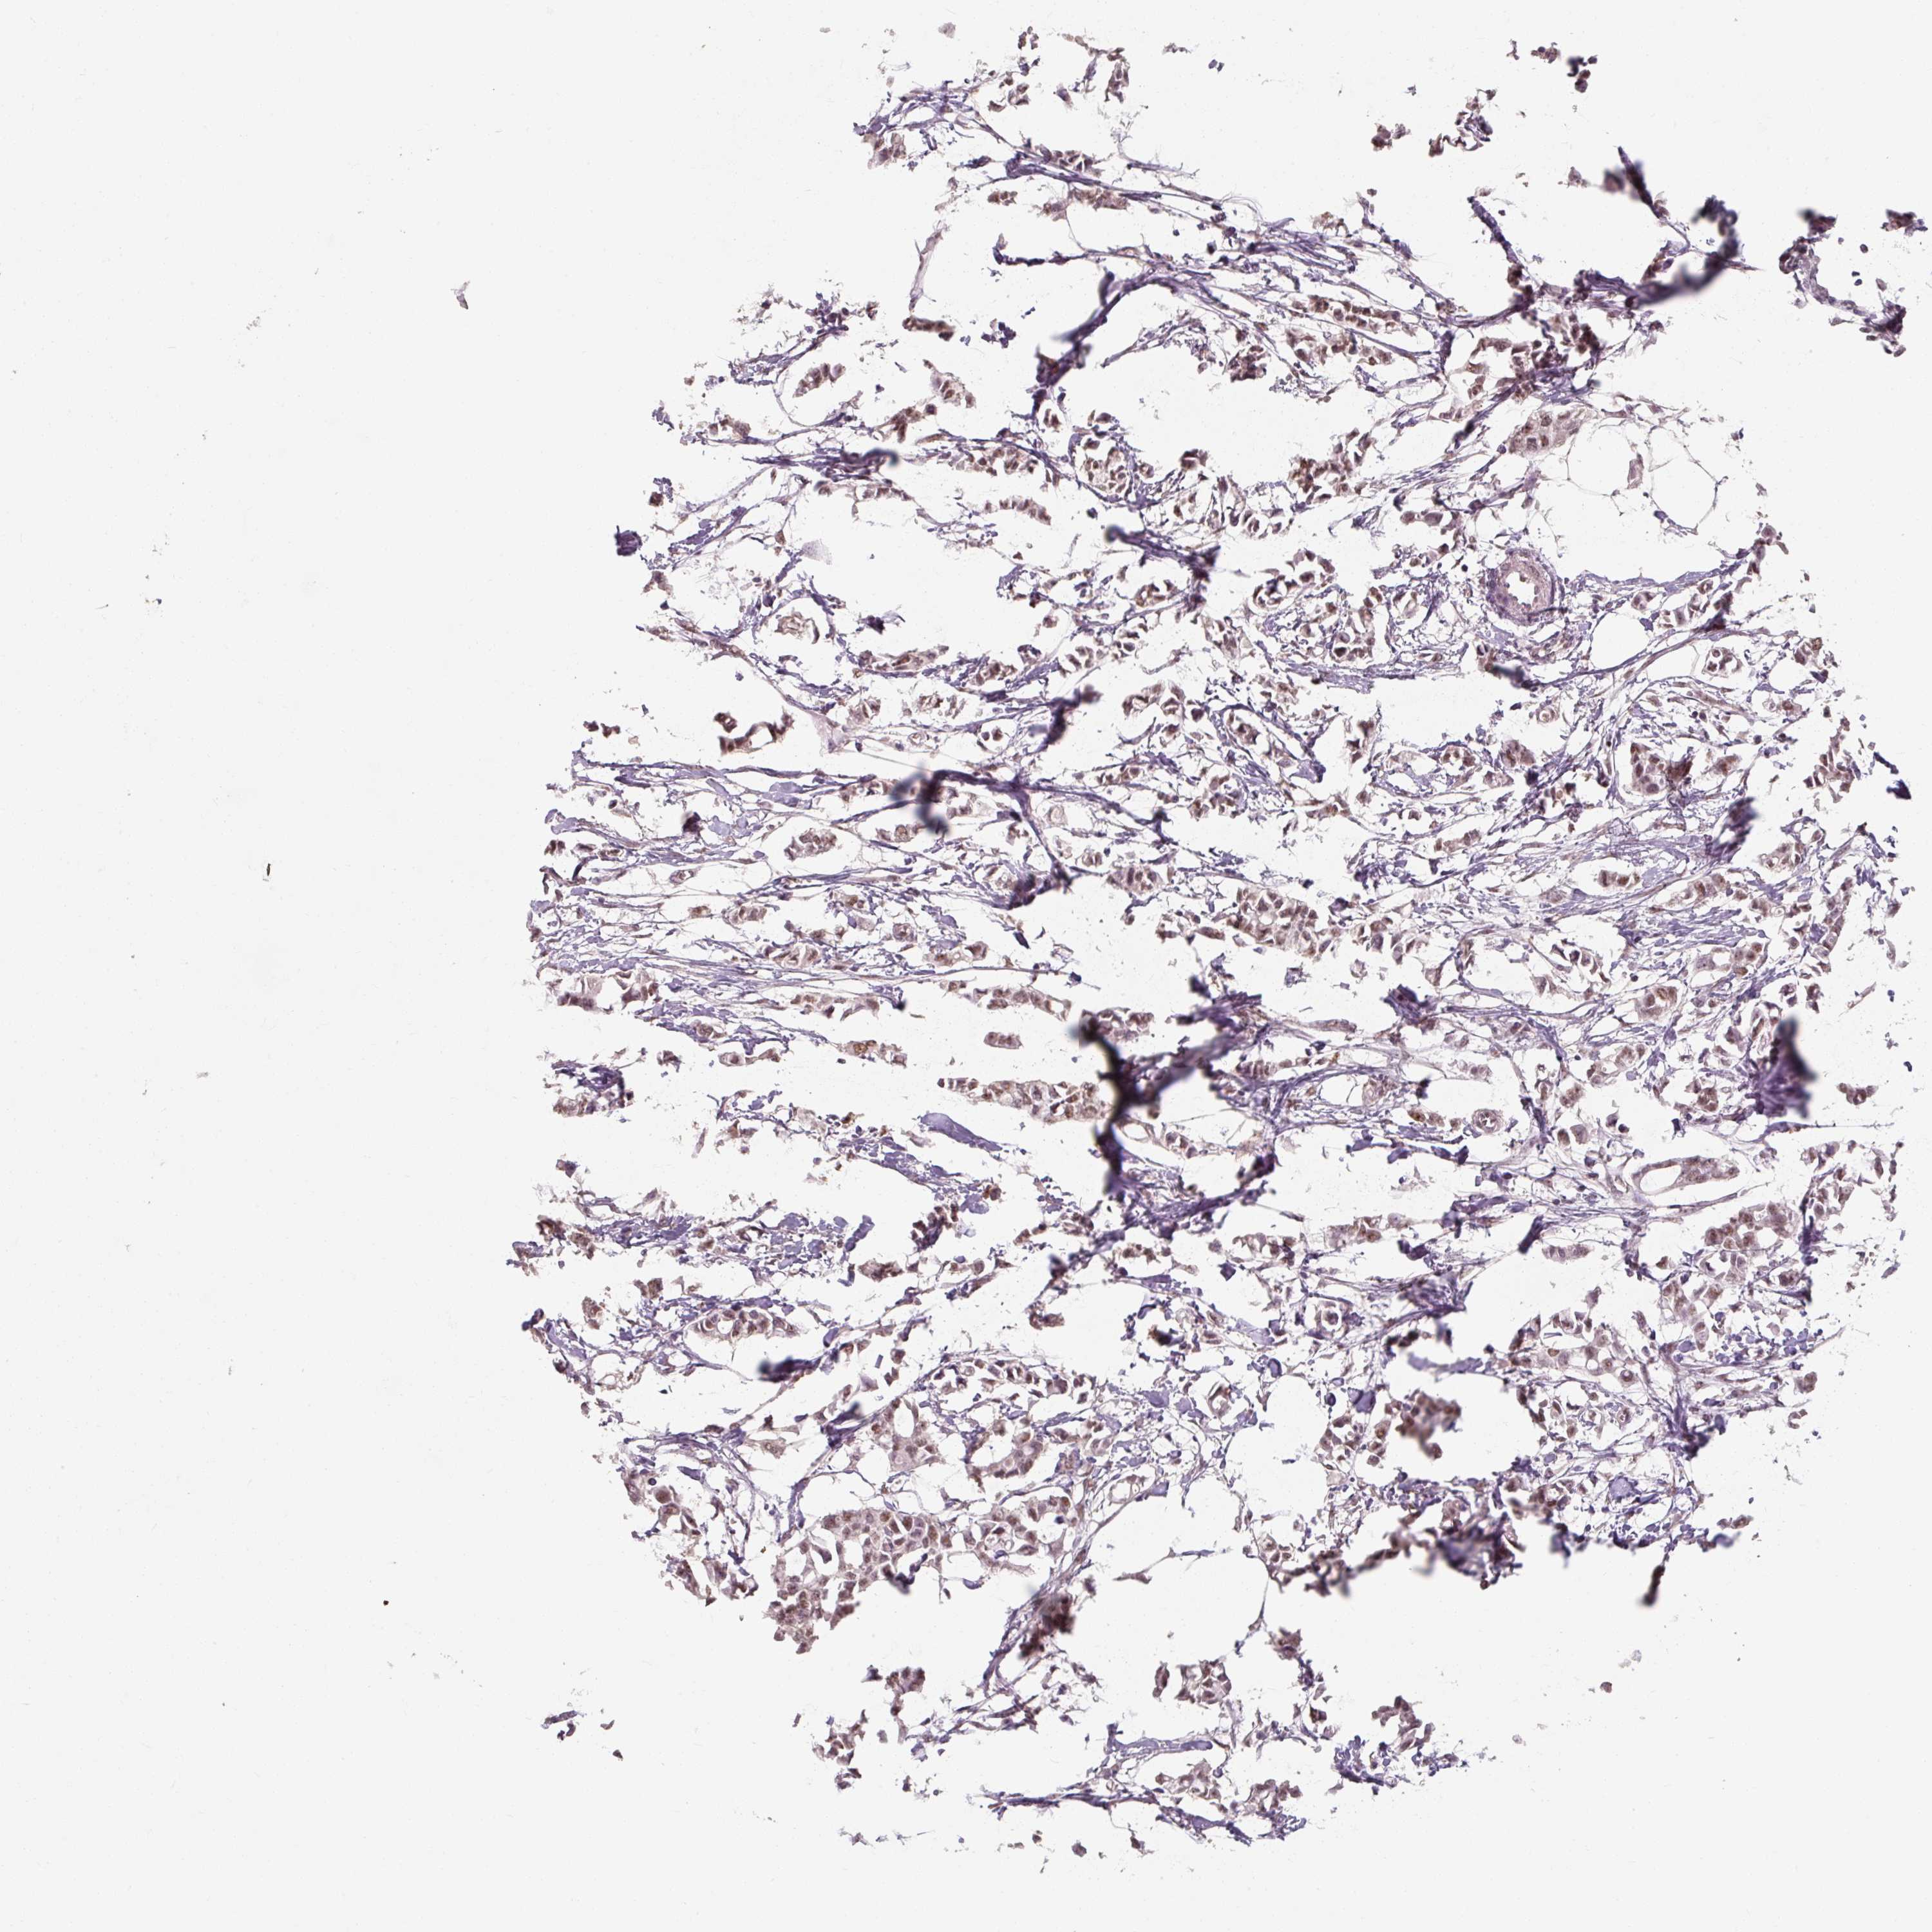

BREAST CANCER - Protein expressioni

A mouse-over function shows sample information and annotation data. Click on an image to view it in a full screen mode. Samples can be filtered based on level of antibody staining by selecting one or several of the following categories: high, medium, low and not detected. The assay and annotation is described here.

Note that samples used for immunohistochemistry by the Human Protein Atlas do not correspond to samples in the TCGA dataset.

Antibody stainingi

Antibody staining in the annotated cell types in the current human tissue is reported as not detected, low, medium, or high, based on conventional immunohistochemistry profiling in selected tissues. This score is based on the combination of the staining intensity and fraction of stained cells.

Each image is clickable and will lead to virtual microscopy that enables deeper exploration of all samples and also displays staining intensity scores, fraction scores and subcellular localization as well as patient and tissue information for each sample.

Antibody HPA053653

Staining

High

Medium

Low

Not detected

Intensity

Strong

Moderate

Weak

Negative

Quantity

>75%

75%-25%

<25%

None

Location

Nuclear

Cytoplasmic/membranous

Cytoplasmic/membranous,nuclear

Duct carcinoma

Lobular carcinoma